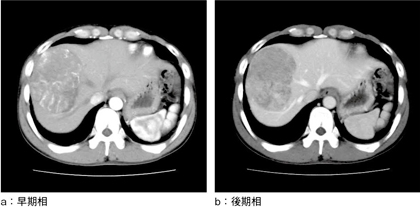

図1 術前CT

肝S8に径8cmの腫瘍を認める。早期相(a)で濃染し,後期相(b)では低吸収を呈して中肝静脈を越えてS4に張り出している。